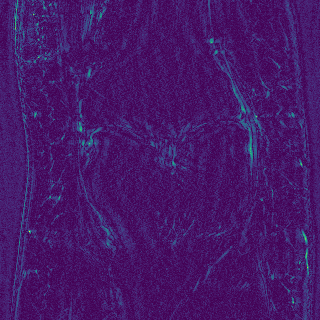

Edge preserving has always been a crucial concern in the design of reconstruction models. To improve the quality of reconstructed images and preserve image edges, some works suggested introducing edge priors in the original restoration problem to preserve image edges [4, 34]. However, they will suffer from complicated algorithm design and time-consuming training processes. Recently, some more efficient methods have been proposed to use edge maps as external guidance for image restoration. For example, Yang et al. [48] used off-the-shelf edge detectors to extract image edges from the degraded images. Fang et al. [12] predicted image edges by constructing an edge reconstruction network. Huang et al. [18] designed a novel dual discriminator GAN framework for solving fast multi-channel MRI, in which one GAN network is built for edge information enhancement. Inspired by these methods, we also consider introducing image edge prior as external guidance to MRI reconstruction since 1) image edges are prominent and distinguishable features in MRI (see Fig. 1), which can serve as a good guide to the model to recover high-frequency details; 2) the ground truth edges can be easily fetched via ordinary edge extraction operators, like Canny, Sobel, and Prewitt, which means that the edge maps can be learned in a data-driven manner. However, how to effectively utilize image edge priors to guide image reconstruction still remains a challenge. In some methods, edge information was simply concatenated with the input image and passed to the next stages. Though this is a simple way to utilize the edge priors, it may not give full play to the guiding role of the edge priors. Therefore, in this work, we want to explore a more efficient and effective mechanism to fully take advantage of image edge priors.

fastMRI is a large-scale MR dataset jointly established by Facebook AI Research and NYU Langone Health. It provides both knee and brain datasets for evaluation. In our work, we use the multi-coil knee dataset, which was acquired on three clinical 3T systems or one clinical 1.5T system using a 15-channel knee coil array. The dataset includes data from two pulse sequences, yielding coronal proton-density weighting with (PDFS) and without (PD) fat suppression. As is shown in Fig. 1, PD images usually contain more structural and prominent edge features than PDFS images, which suggests that it is more challenging to use edge guidance on PDFS datasets. Therefore, we explore the effectiveness of EAMRI on these two modalities. Following [13], for both PD and PDFS knee datasets, we separately filter out 227 volumes (8332 slices) for training and 24 volumes (1665 slices) for testing. The dataset is centrally cropped to .